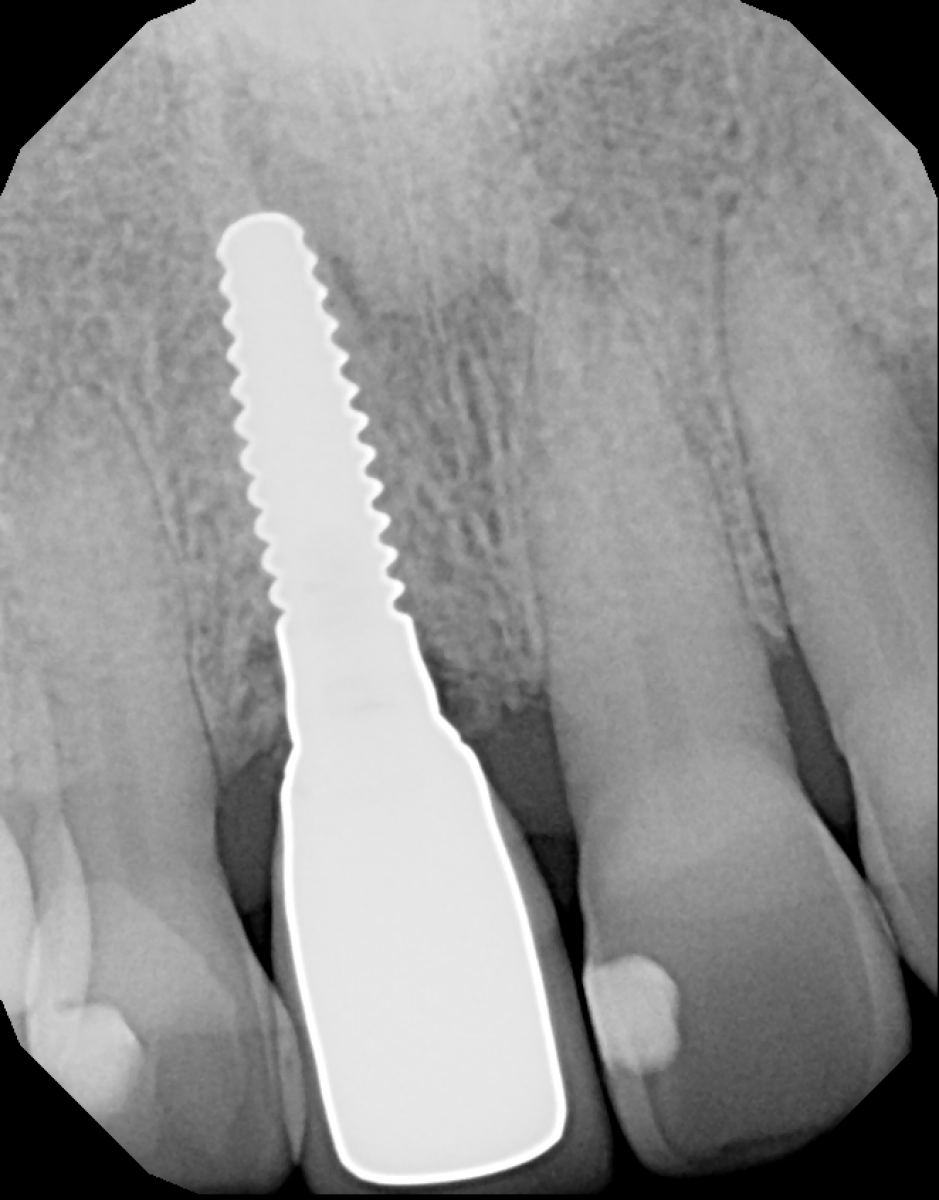

A 55-year-old male patient presented to our clinic seeking a solution for his failing anterior tooth (Figure 1). The tooth had been previously endodontically treated; currently it protruded coronally 1-2mm, had vertical bone loss in the mesial and grade II-III mobility (Figure 2).

After administering local anesthesia, the tooth was atraumatically extracted, the socket was curetted clean and the presence of a complete buccal wall was confirmed. Osteotomy was done according to manufacturer protocols, with copious irrigation and a 3.5 x 12mm Zeramex XT ceramic implant was placed (Figure 4) at 50 N/cm2 final torque.